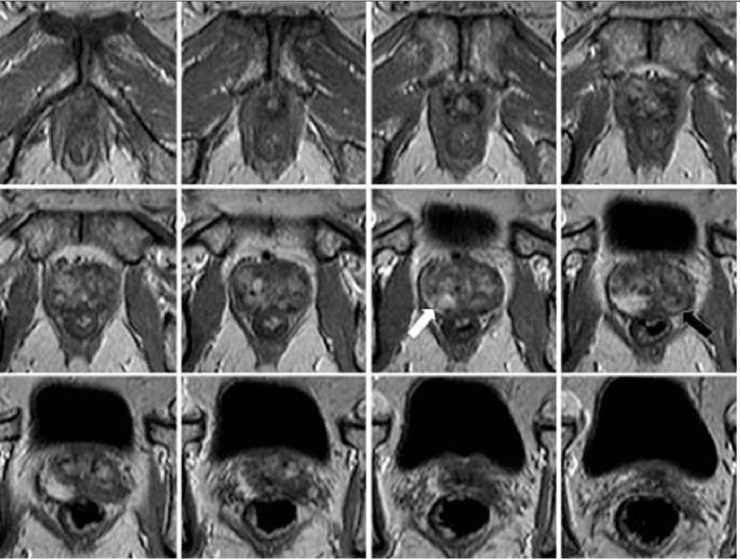

Dr Bounhir BOUMEHDI : Les radiologues mettent en avant les progrès réalisés dans le domaine de l'imagerie afin de plaider pour une révision des pratiques. Car, depuis cinq ans à six ans, nous avons amélioré la détectabilité des tumeurs de la prostate grâce à des techniques d'IRM fonctionnelles. L’IRM de perfusion permet de repérer les zones très vascularisées, notamment les tumeurs, tandis que l'IRM de diffusion permet de distinguer les tissus de nature cancéreuse. Par ailleurs, Il y a un fort mouvement de la part des experts américains et européens en faveur d'une détection primaire par IRM en même temps que le toucher rectal et le taux de PSA. Mais on a encore besoin de voir les résultats des études en cours, comme celles aux États-Unis et au Royaume-Uni, pour déterminer si cette IRM avant la biopsie permet de détecter tous les cancers évolutifs et de réduire la mortalité tout en évitant les surtraitements.